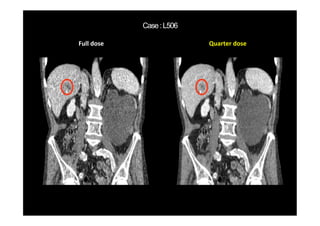

Routine dose Quarter dose

(Kang, et al, Medical Physics 44(10) 2017)

Routine dose AAPM-Net results

WavResNet results

(Kang et al, TMI, 2018)

MBIR Our latest Result

C D WavResNet results

Full dose Quarter dose